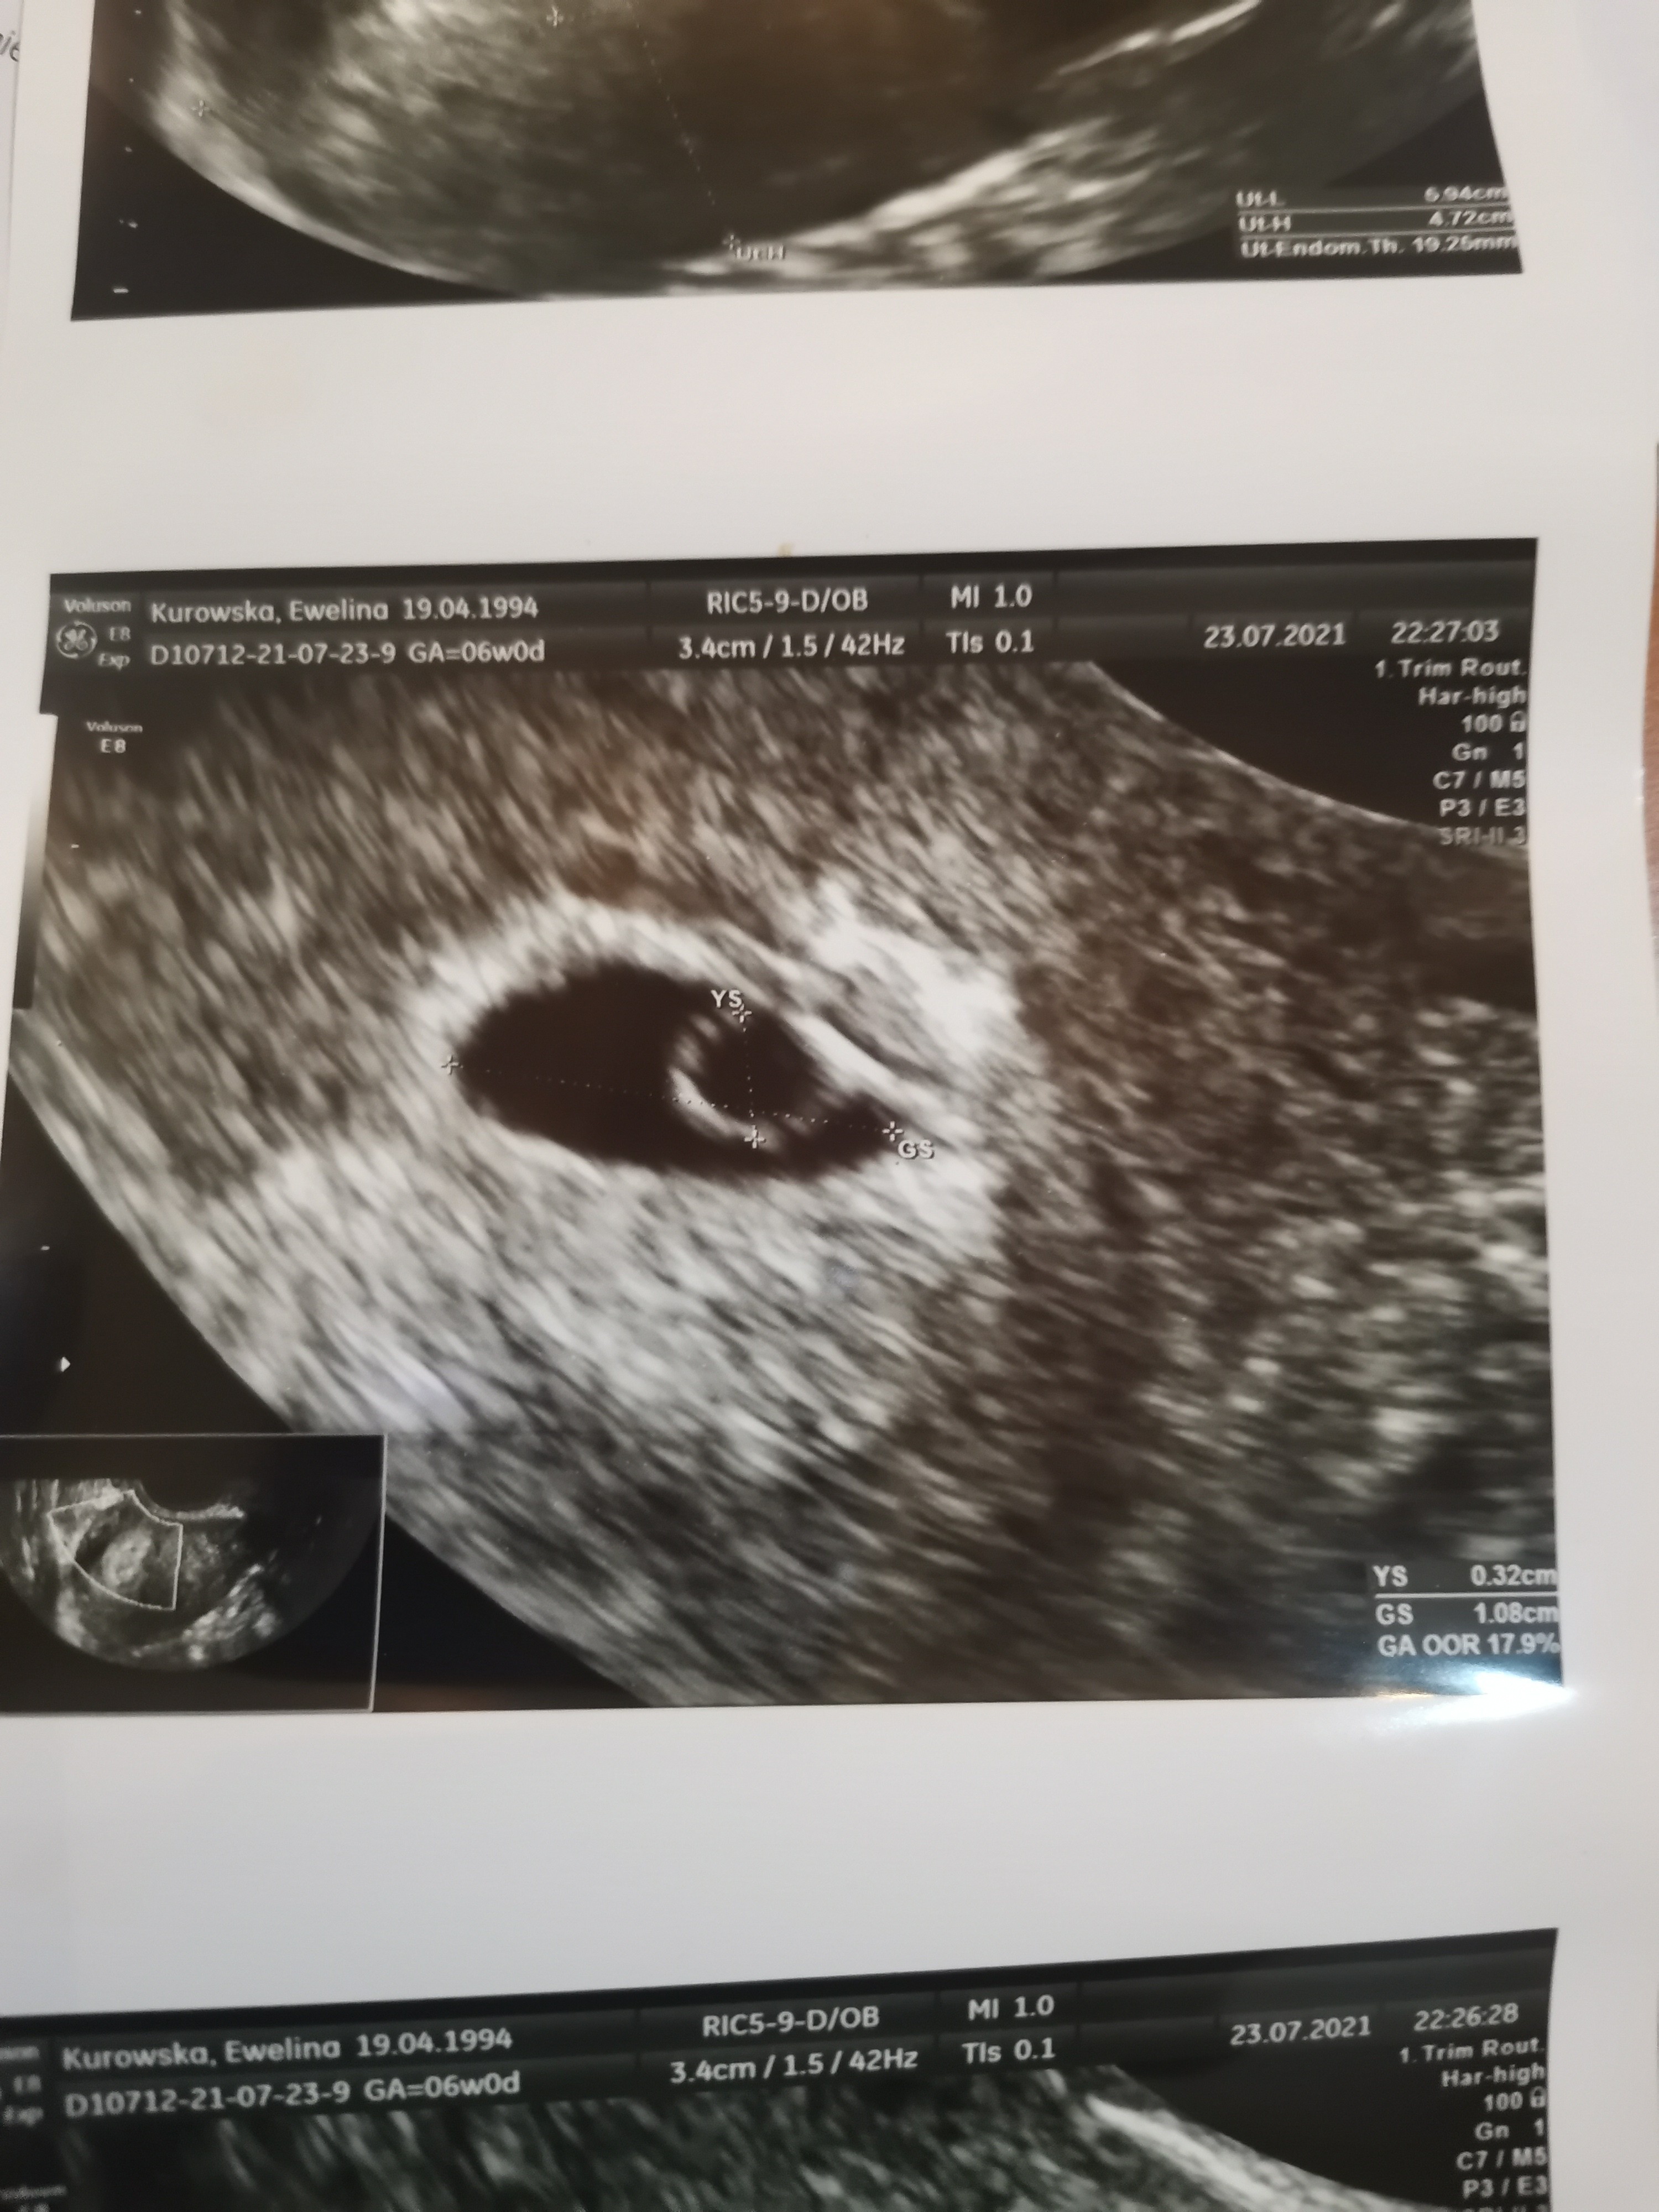

Niewidoczny zarodek.

• IMG_20210723_214712.jpg

IMG_20210723_214712.jpg

1,4 MB · Wyświetleń: 256

Do 25mm jeśli nie pojawi się żółtkowy to niestety nic się juz nie rozwinie dalej.

Szkoda że nie wiesz czy był ten żółtkowy bo on bardzo dużo daje

U autorki skoro był żółtkowy to zarodek powinien pojawić się po tym po kilku dniach